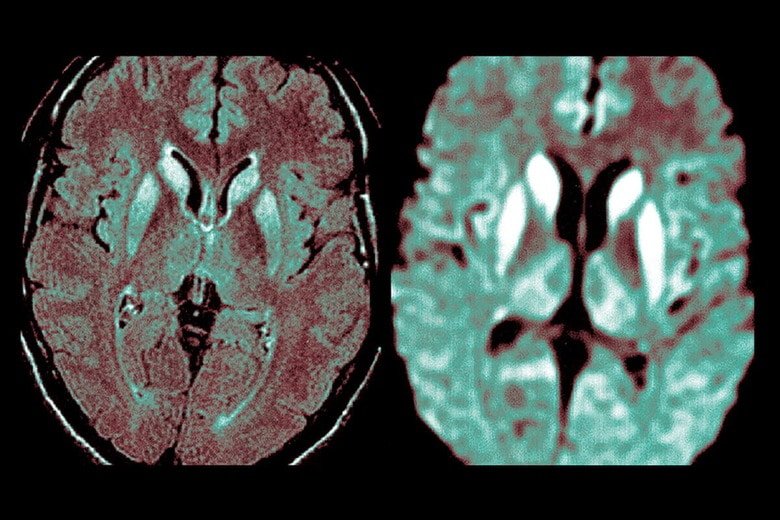

プリオン病は伝達性海綿状脳症(TSE)とも呼ばれる非常にまれな中枢神経疾患。異常プリオンタンパクが原因で、数年から数十年の長い潜伏期間を経て症状が現れると急速に進行し、不随意運動、認知症、運動失調、人格変化などが起こり、100%死に至る。

ヒトのプリオン病である変異型クロイツフェルト・ヤコブ病(vCJD)は、牛海綿状脳症(BSE)に感染した牛を食べることでかかると考えられており、2000年代初頭にイギリスを中心に広まり社会問題になった。